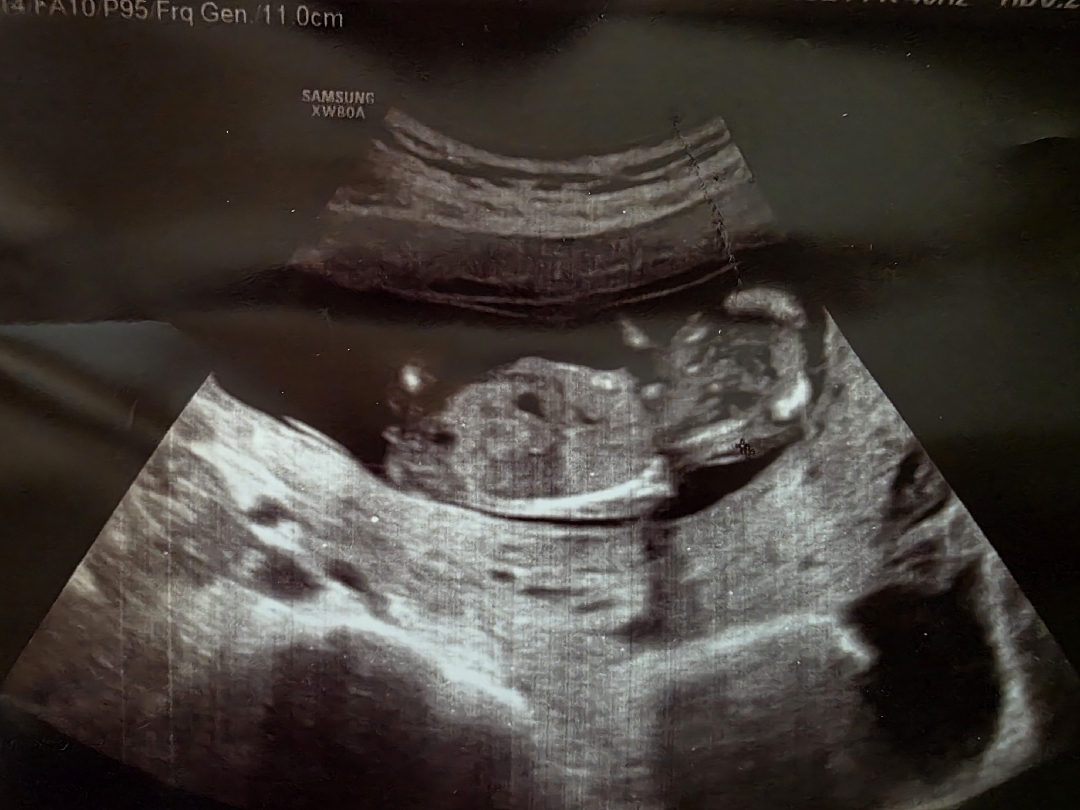

오늘로 12주6일째에요 베동에 성별각도법 해보니 정확하지 않지만 62%로 딸이라고는 하는데 궁금해요ㅜㅜㅜ 이게 그나마 젤 잘나온 사진이에요